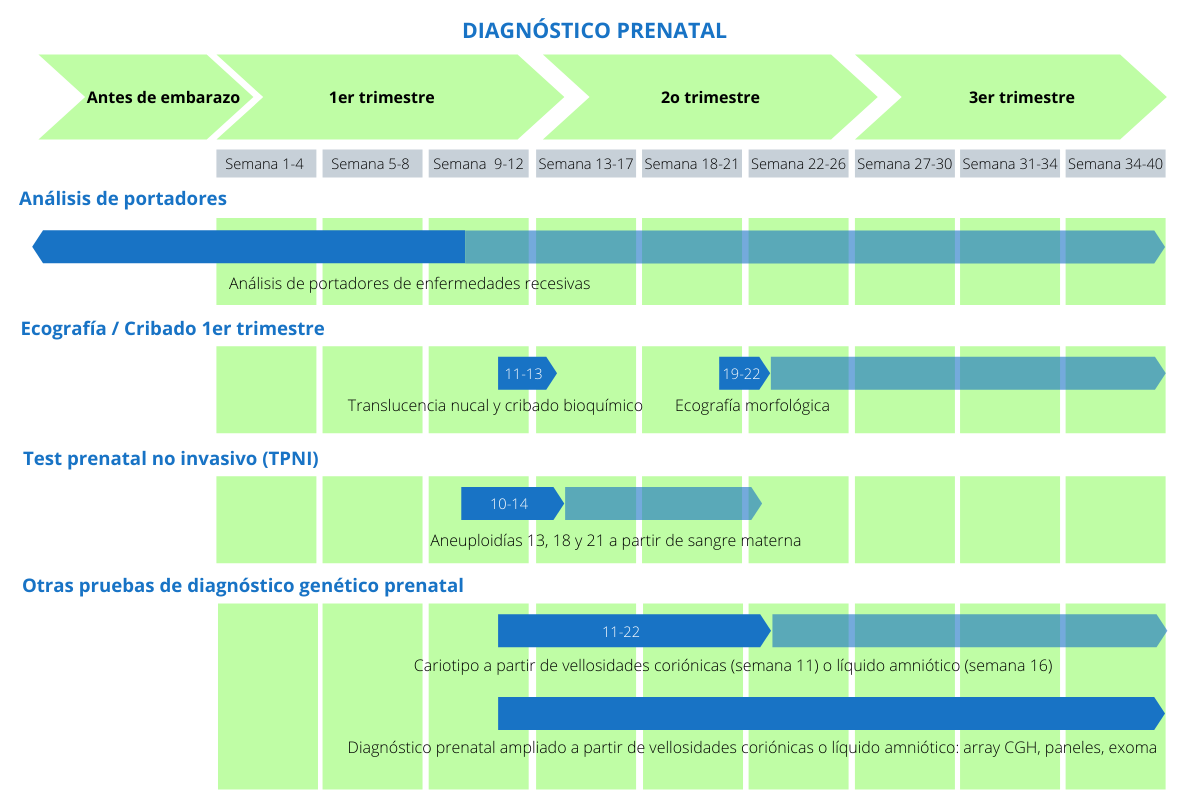

Diagn stico prenatal TPNI y otras pruebas Genosalut